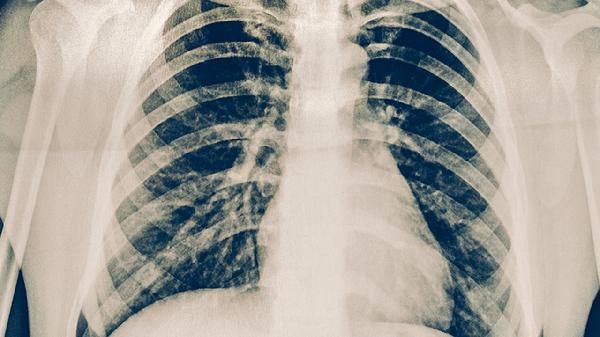

靶向药通过精准作用于肿瘤细胞的特定分子靶点抑制癌细胞生长,相比传统化疗具有副作用小、耐受性好的优势。EGFR突变患者使用吉非替尼片、厄洛替尼片等药物后,肿瘤缩小概率较高,中位无进展生存期可达数月甚至更久。ALK阳性患者服用克唑替尼胶囊、阿来替尼胶囊等药物后,部分患者可实现长期带瘤生存。对于ROS1、BRAF等罕见突变,相应靶向药如恩曲替尼胶囊、达拉非尼胶囊也能发挥一定作用。靶向治疗期间需定期复查影像学及肿瘤标志物,动态评估疗效。